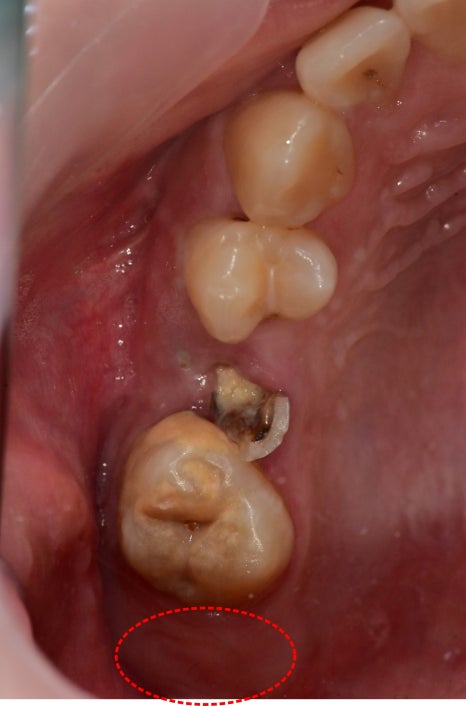

소아에서 맹출 시 잇몸이 치아 일부를 덮는 경우

초등학교 고학년 아이였습니다.

가장 마지막 어금니가 맹출은 되었지만

잇몸이 치아 일부를 가리고 있어서 틈으로

음식물이 제거가 안되어 충치가 생긴 상태였습니다.

잇몸이 가려진 채로는 충치치료가 진행될 수가 없기 때문에

해당 끝 부위를 잇몸을 절제하고 주변 성형을 시행했습니다.

잇몸의 회복력이 워낙 좋다 보니

해당 케이스는 중간에 다시 자라난 잇몸을

재성형술을 한 번 더 시행한 케이스입니다.

치료 완료 후 6개월 체크 시 사진에서는 튼튼한 잇몸이

다시 덮지 않고 잘 위치해 있는 것을 볼 수 있었습니다.